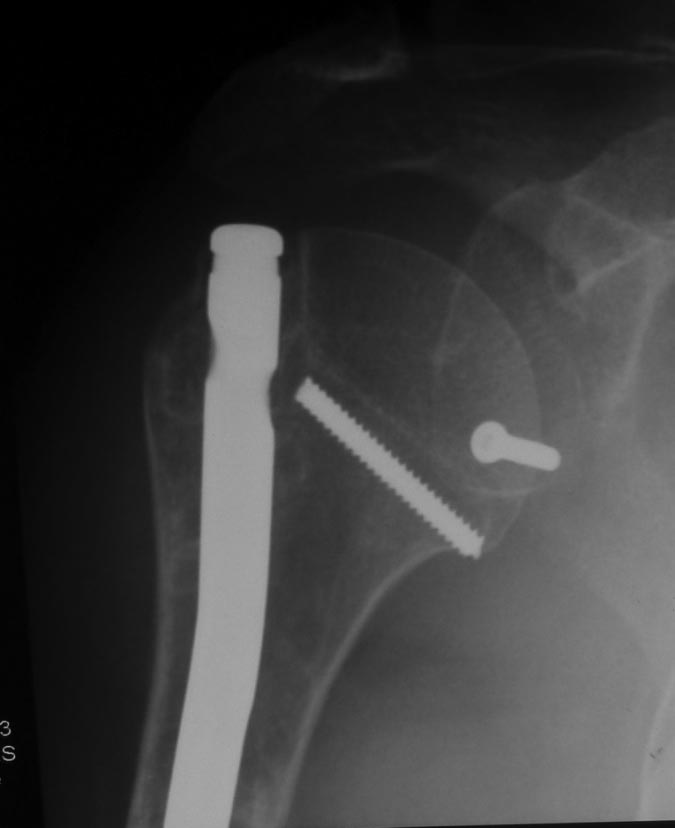

Как бы автор вопроса не убеждал себя, что в ситуации с гвоздем (его длиной, расположением относительно манжеты и бугорков и т.д.) все ясно, при таком качестве представленных рентгенограмм в единственной проекции никакой ясности быть не может.

В качестве примера - случай, который оперировал всего 2 недели назад, после похожего остеосинтеза, выполненного год назад. Пациентке 75 лет, тяжелый РА, легла для решения вопроса о ревизии тазобедренного сустава и заодно пожаловалась на то, что рука "крутиться" сама по себе, не поднимается. И болит, конечно. И посмотрите на разницу в информации на снимках головки плеча в двух противоположных проекциях. Даже комментировать ничего не нужно.